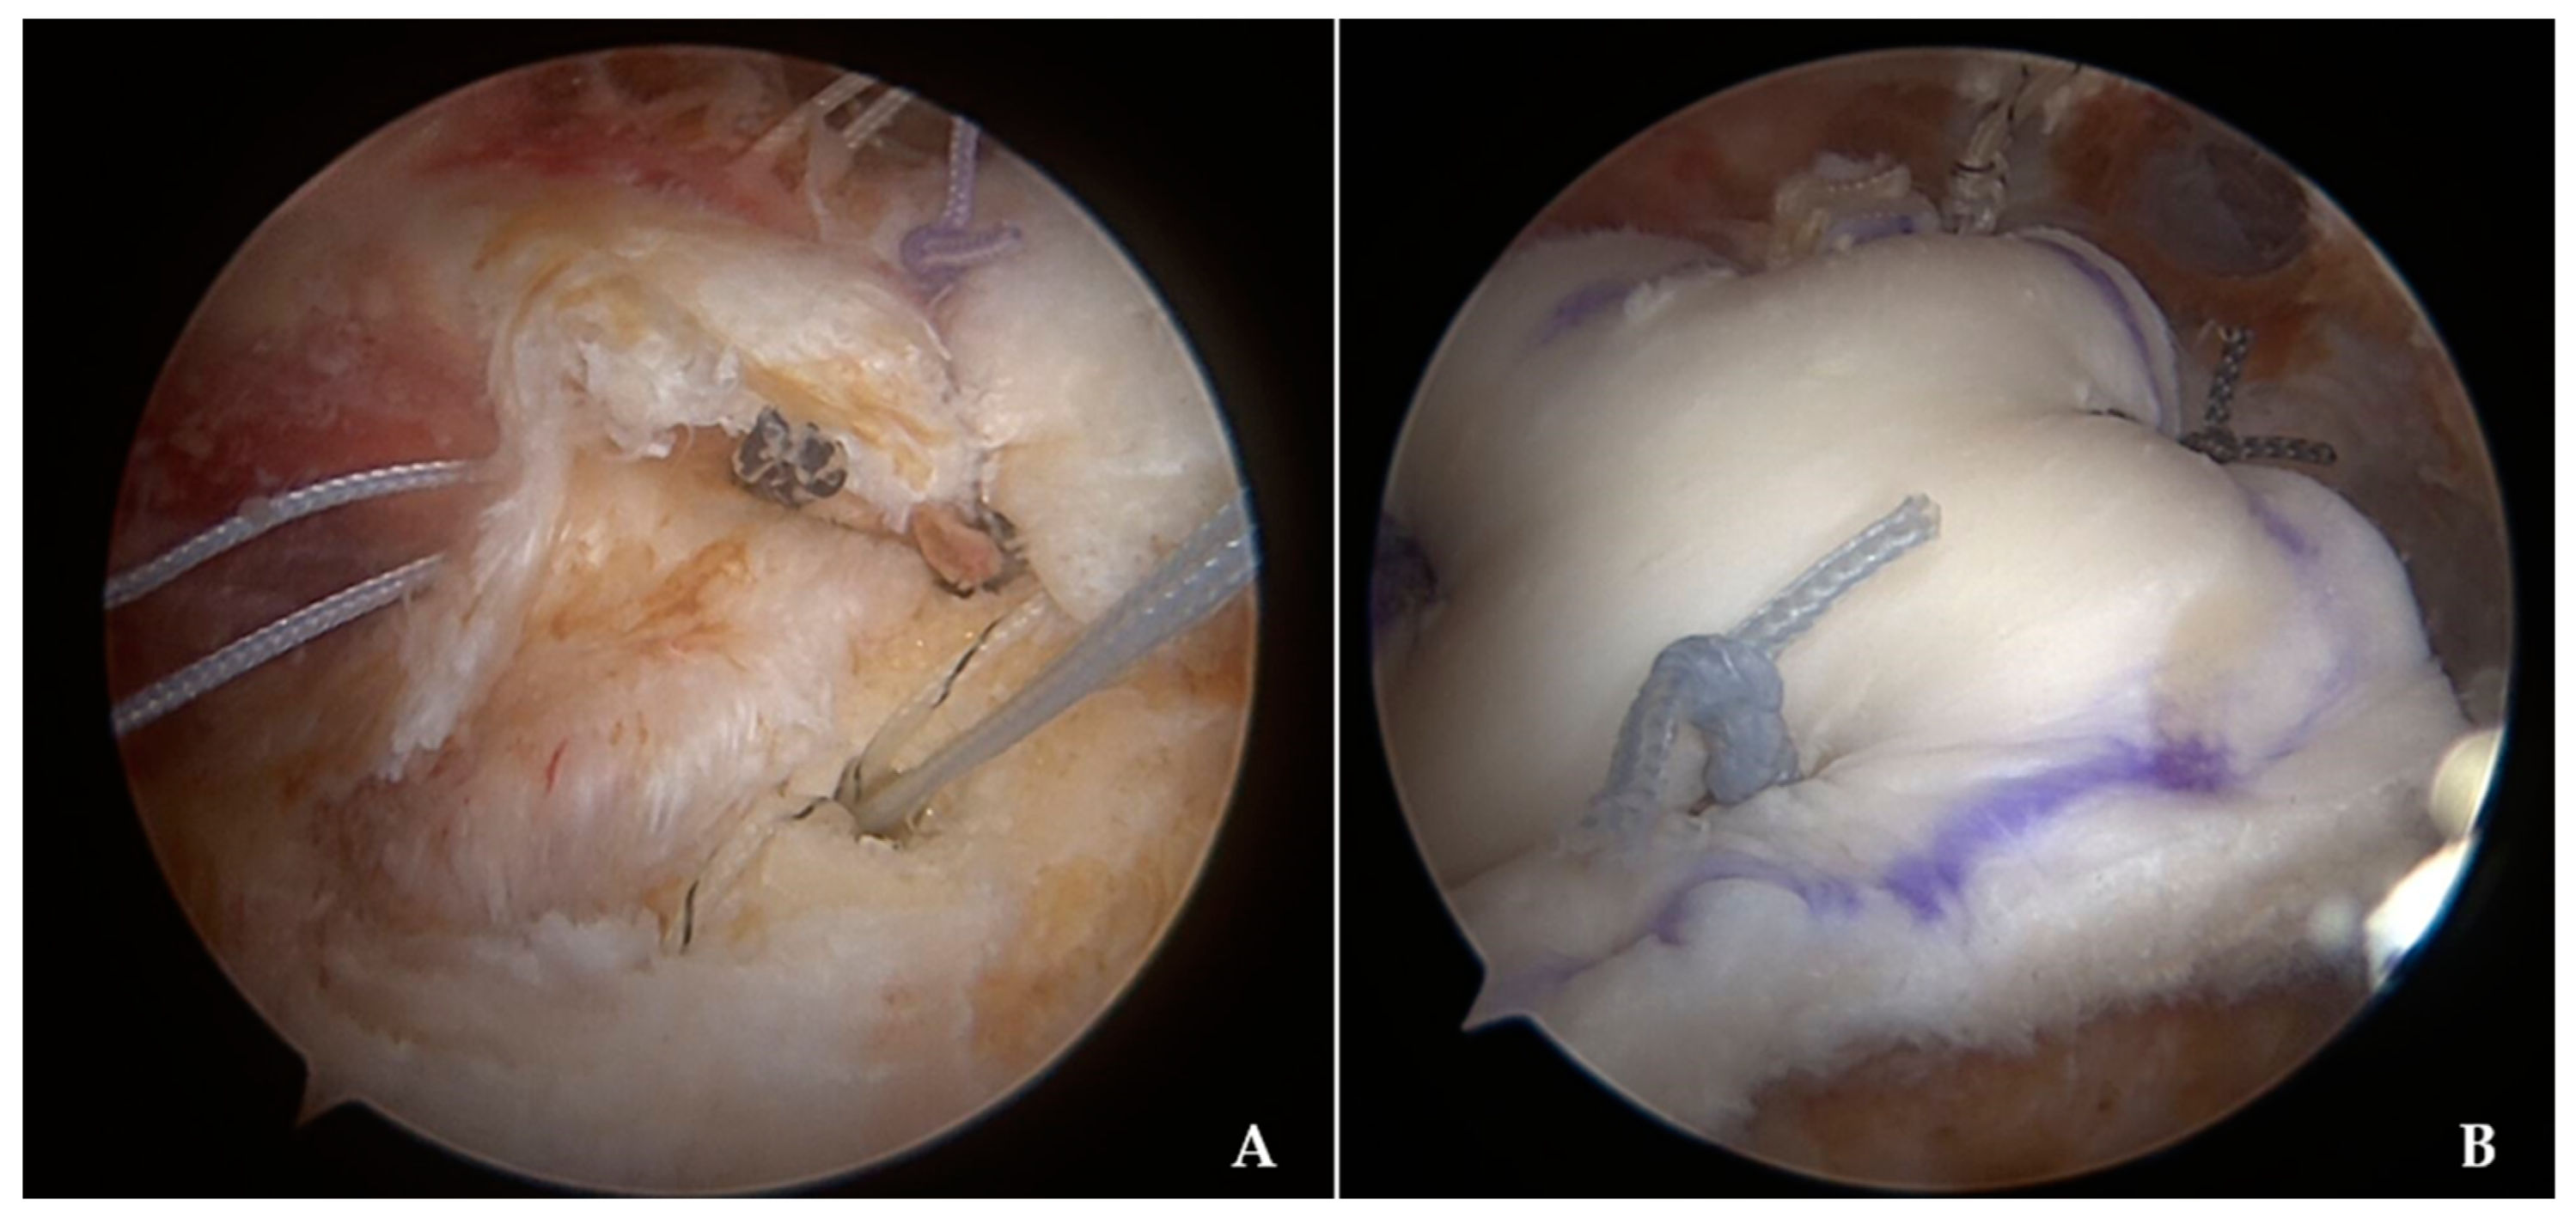

2.3. Surgical Procedure